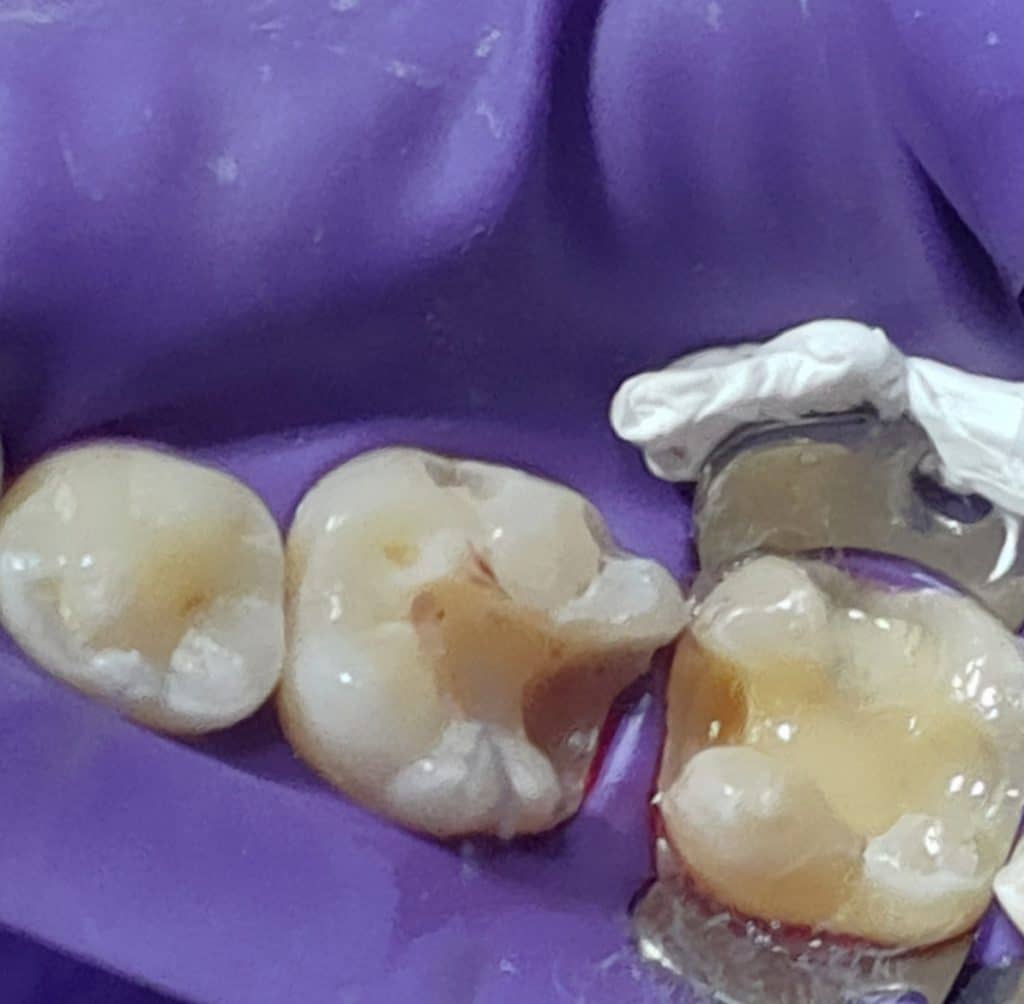

The following case came to dental office complaining from old destructed amalgam restoration.

1- I started removing old restoration with medium size diamond rose head also, removing all undermined enamel

2- cavity design was preformed properly in each tooth

3- pulp liner placed in tooth no;37 after rubber dam insertion and good isolation

4-I tend to restore tooth no,37 first then tooth no,36 using sectional and saddle matrix system form TorVM